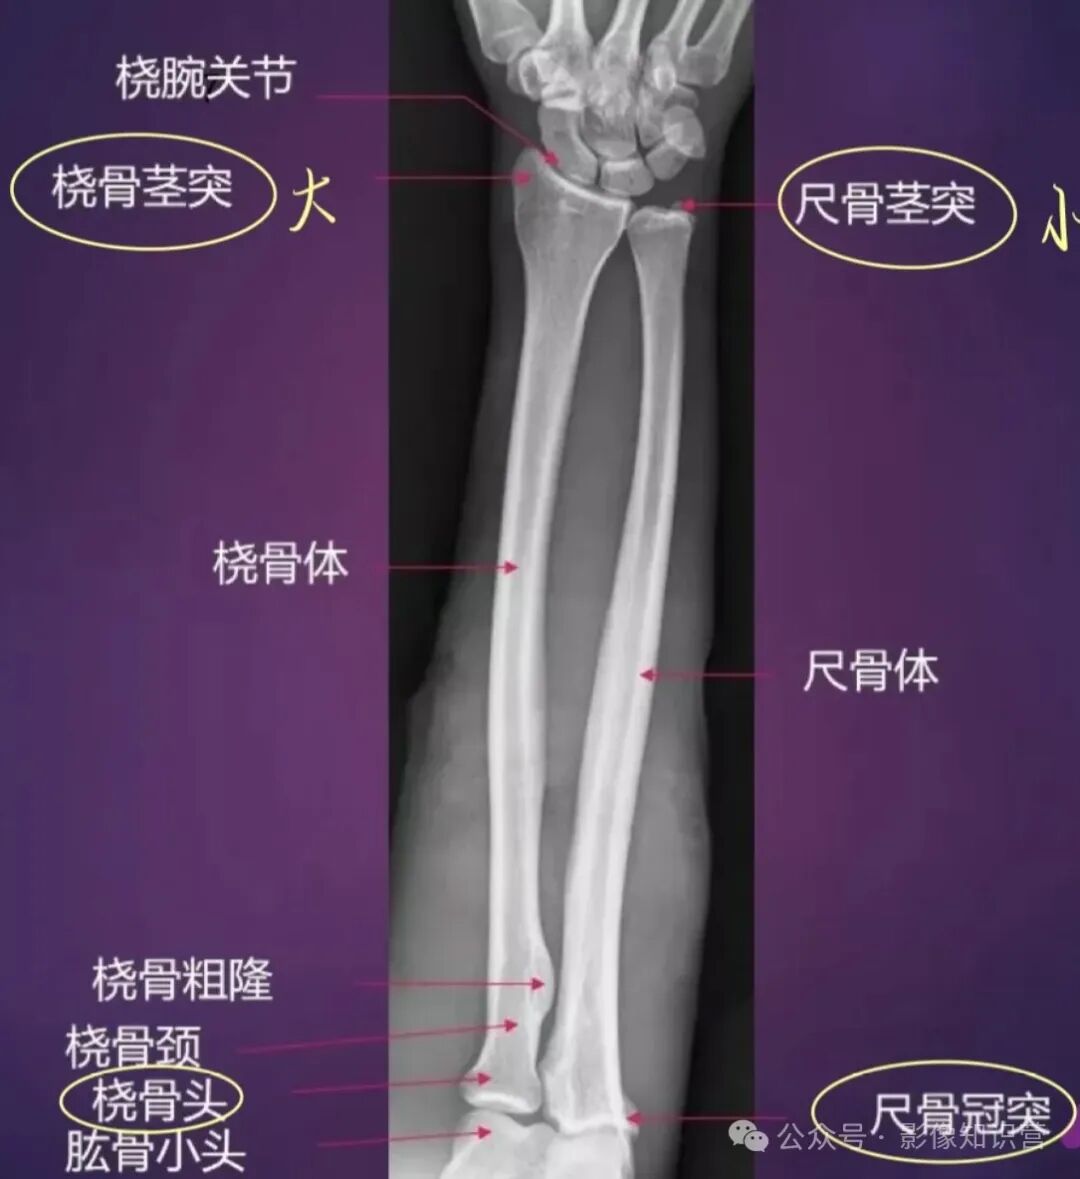

前臂

骨骼组成:桡骨(近端为桡骨头,远端为桡骨茎突)和尺骨(鹰嘴、尺骨茎突)。

影像要点:观察桡骨和尺骨的解剖对位,如桡骨茎突较尺骨茎突低约1cm。

桡骨:位于前臂外侧。上端为桡骨头,头上面的关节凹与肱骨小头相关节。桡骨下端外侧有茎突,内侧面有尺切迹与尺骨头相关节。

尺骨:位于前臂内侧。冠突前有尺骨粗隆,冠突外有桡切迹与桡骨头相关节。尺骨下端为尺骨头,其内侧有尺骨茎突。